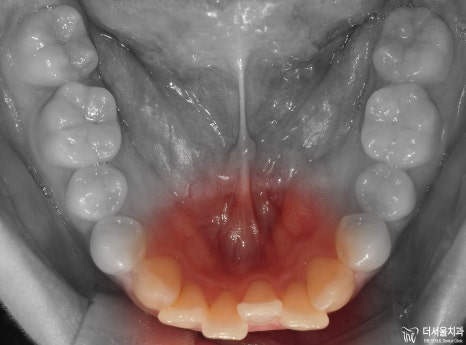

먼저 교합면에서 보게 되면, 앞니들의 총생이 관찰됩니다.

측면에서는 확연히, 돌출입 형태를 확인하실 수 있습니다. 이렇게 앞니들이 앞으로 뻐드러져

있는데 심미선을 기준 으로 봤을 때 입술의 위치가 그대로 예쁜 곳에 있는 걸 보면

연조직이 얇아서 가능하다라는 것을 추측할 수 있겠네요.

아울러, 이 분의 경우에는 비발치 교정 으로 치료를 하길 원하셨었습니다.